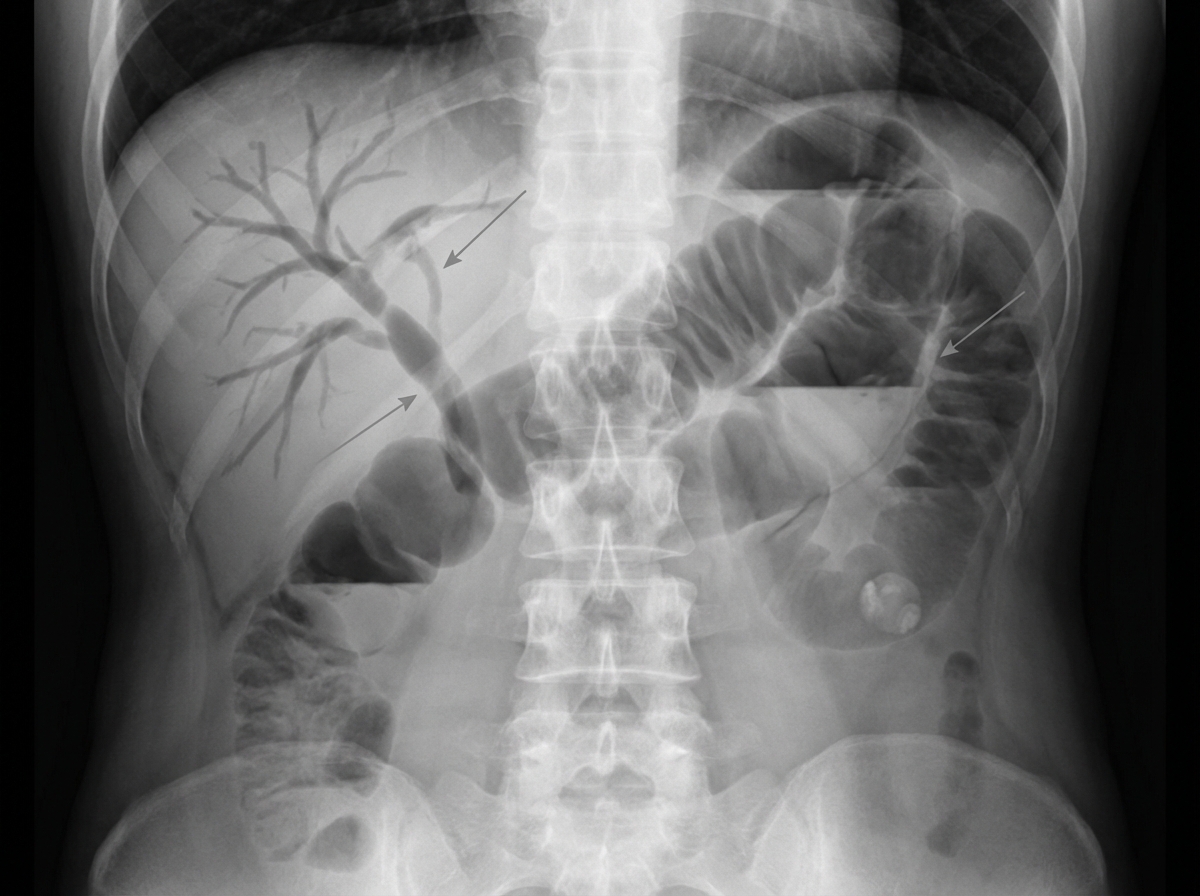

- Imaging: Abdominal/Pelvic CT with contrast is the gold standard.

- Key CT Findings: Sigmoid wall thickening (>4 mm), pericolic fat stranding, abscess, fistula.

- Fistula: Abnormal connection to adjacent organs.

- Colovesical: Most common; presents with pneumaturia, fecaluria.